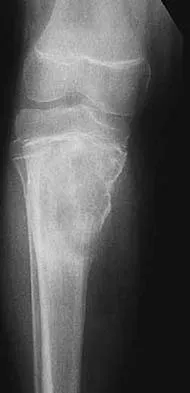

This article provides essential research regarding The Growing Problem of Osteoporosis: Your Guide to Prevention & Treatment. Osteoporosis is a condition weakening bones and causing brittle fractures, impacting quality of life with pain, disability, and even death. The problem of osteoporosis is escalating, driven by an aging population, lifestyle changes, and improved diagnosis. Addressing this serious health concern is crucial for improving public health and well-being across all ages.